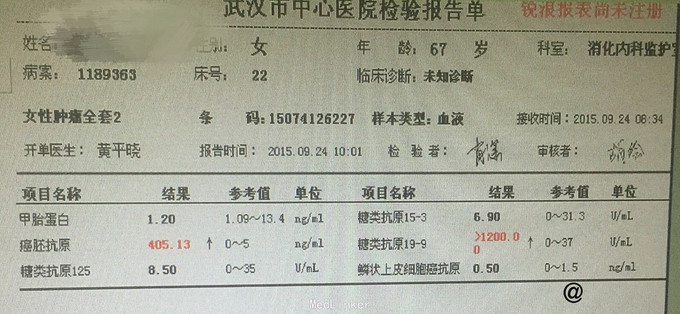

入院后完善相关检查 血常规:白细胞计数 13.84 ↑ 4~10 10^9/L。尿液分析及尿沉渣:白细胞 +- 阴性隐血 +- 阴性蛋白质 1+ 阴性糖 4+ 阴性,酮体 2+ 阴性。 生化全套2:白蛋白 32.9 ↓ 35~55 g/L球蛋白 39.9 ↑ 20~35 g/L白球比值 0.82 ↓ 1~2.5葡萄糖 20.85 ↑ 3.82~6.1 mmol。血脂肪酶及淀粉酶正常。红细胞沉降率 53 0~20 mm/h。糖化血红蛋白 11.7 ↑ <6 % 肿瘤全套2:癌胚抗原 405.13 ↑ 0~5 ng/ml,糖类抗原19-9 >1200.00 ↑ 0~37 U/mL。 头颅CT平扫未见明显异常。 胸部+上腹部CT提示:1.胃积气扩张,余上腹部CT平扫未见明显异常。2.肺气肿,支气管炎肺部表现;3.双肺间质性肺炎;4.主动脉硬化;5.主动脉窦致密影,考虑瓣膜钙化。 胰腺增强:1 胰腺CT增强未见明显异常。2 右肾小囊肿。 肠镜检查:大肠黑变病。胃镜检查:浅表性胃炎(2级)。 复查癌胚抗原 383.42 ↑ 0~5 ng/ml糖类抗原19-9 >1200.00 ↑ 0~37 U/mL,仍旧显著升高,为进一步排除肿瘤行病变,遂行盆腔磁共振检查:1.盆腔右侧占位,肿瘤性病变不除外,建议增强扫描。2.右侧附件区结节影,建议增强扫描。3.子宫肌层信号欠均匀,不除外腺肌病可能。4.盆腔少许积液。